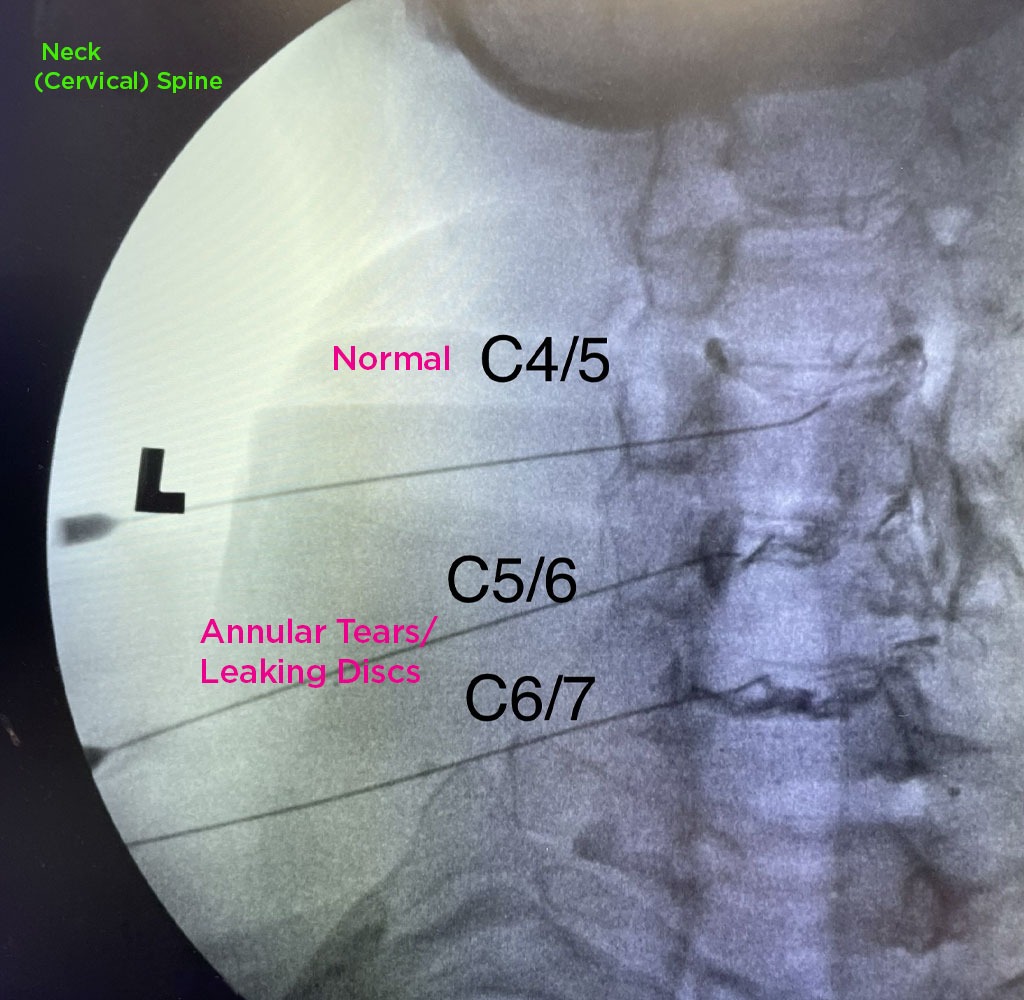

Annulargram™ Gallery

This gallery contains Annulargram images.

The Annulargram is a pain-free test and a crucial part of the DISCSEEL Procedure that identifies even the most subtle tears in spinal discs that MRI and discography cannot.

During the Annulargram, every disc in the region is tested to address current and future pain issues by finding even the most subtle annular tears. With the Annulargram, damaged spinal discs are pinpointed and precisely treated with Fibrin, leaving all healthy discs as they are.

Tears in spinal discs cannot be seen on MRI nor discography. As shown: leaky discs are only visible on the Annulargram.